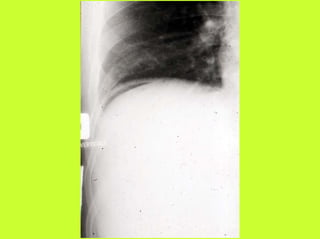

3) RADIO (PNO)

RADIOGRAPHIES

ABDOMEN SP -scanner

PNEUMOPERITOINE SUR SUJET DEBOUT

" Croissant gazeux sous diaphragmatique

" Disparition du niveau hydroaérique gastrique

PNEUMOPERITOINE SUR SUJET COUCHE

" Visibilité du ligament triangulaire du foie

" Visibilité anormale des parois intestinales

" Image aérique pré-hépatique

"Pneumatisation de MORRISSON

(cul de sac inter-hépato-rénal)